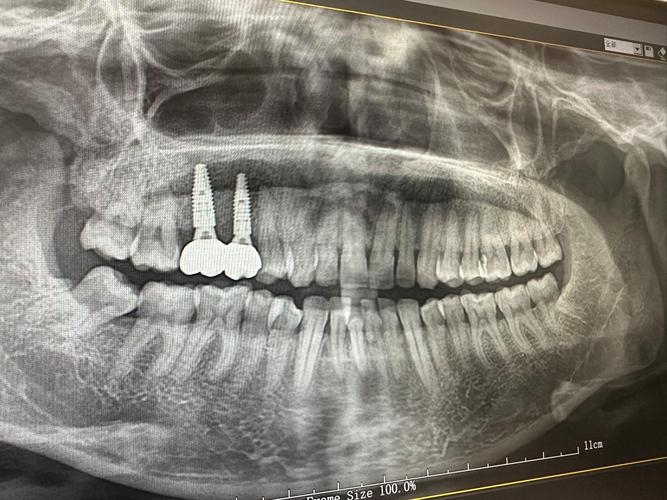

术前检查是种植成功的基础,患者需进行口腔全景片、CBCT影像检查,评估牙槽骨的高度、厚度、密度,以及邻牙和神经管的位置;同时需排查全身性疾病,如未控制的糖尿病、严重高血压、骨质疏松等,这些疾病可能影响骨结合速度,口腔卫生状况(如是否有牙周炎、牙龈炎)也需先进行治疗,确保种植环境健康。

手术植入是种植牙的关键步骤,在局部麻醉下,医生切开牙龈,暴露牙槽骨,使用专用种植机将种植体植入预定位置,随后缝合牙龈,手术时间通常为30分钟-2小时(根据种植数量而定),过程中患者无明显疼痛,术后需服用抗生素预防感染,7-10天拆线,期间避免食用过硬、过热食物。